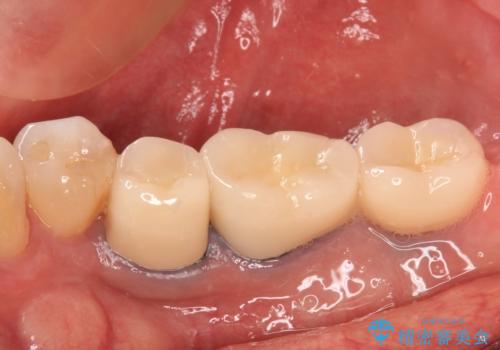

- 奥歯の欠損部へのインプラント治療を希望して来院された患者様です。

抜歯をしてから長年経過しており、レントゲンからは十分に骨があることが分かっていたため、速やかに治療を開始することとしました。

インプラント治療に当たり、手前の銀歯2本の審美回復も希望されたため、3歯のオールセラミッククラウンによる補綴治療を行うこととしました。

通常、奥歯を抜歯した状態で長年放置すると、咬み合う歯が伸びてきて、咬み合わせが乱れてしまうことが多いです。そのような場合には、部分的な矯正治療などが必要となるのですが、こちらの患者様は幸運なことに咬み合わせが乱れていなかったため、インプラント埋入から速やかに補綴治療を行うことができました。